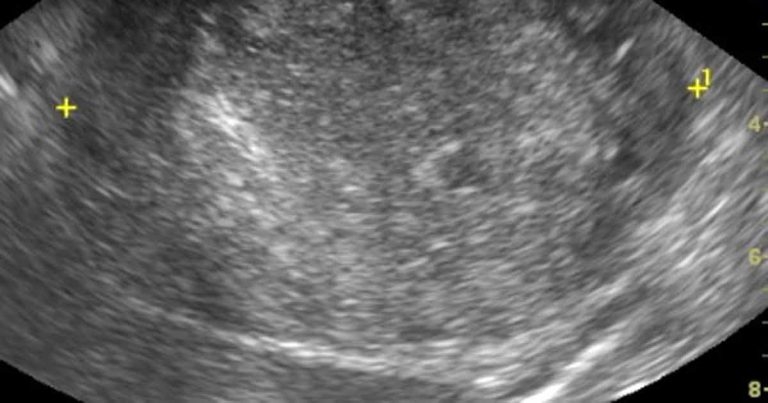

Figure 2. A long-axis ultrasound image of the right kidney of a dog. The central region of the kidney is obliterated by a rounded heterogenous, largely hyperechoic mass lesion. Histopathology of the tumour after excision showed this to be a renal carcinoma.

Renal ultrasound is non-invasive, not painful and useful to identify renal structural abnormalities. Ultrasound does not provide information about renal function. CKDs that can result in structural changes include renal tumours (including lymphoma and adenocarcinoma; Figure 2), renal dysplasia, pyelonephritis, nephrolithiasis and polycystic kidney disease. Subtle structural changes are seen with conditions such as chronic interstitial nephritis and glomerular diseases until later in the disease process when the corticomedullary definition is reduced, and the kidneys become small, with irregular contours.